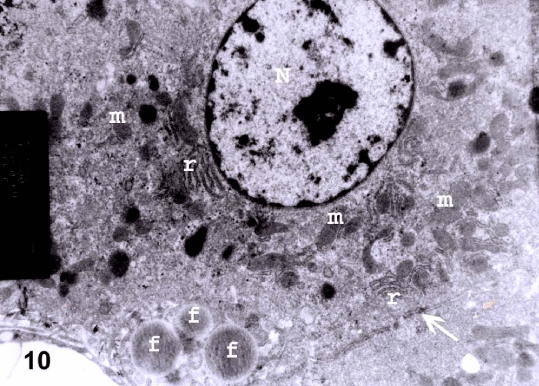

| Figure 10: An electron micrograph from a section in the liver of prophylactic group III showing hepatocyte with euchromatic nucleus (N), regular rough endoplasmic reticulum (r) and mitochondria (m). Cytoplasmic fat globules (f) are noticed. Tight junction (arrow) between two hepatocytes is also noticed (TEM X 11000). |